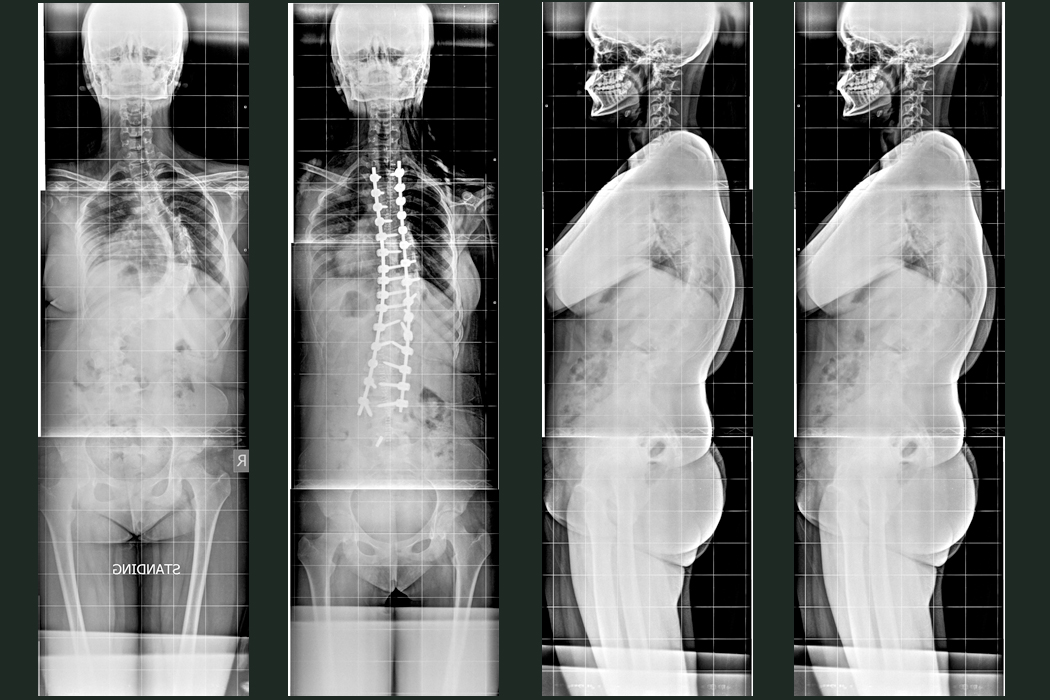

Patient B

A 12 year old school girl was presented with severe deformity of back for the last 2 years. She was initially managed with Halo application followed by Posterior Scoliosis correction done in the year 2021.